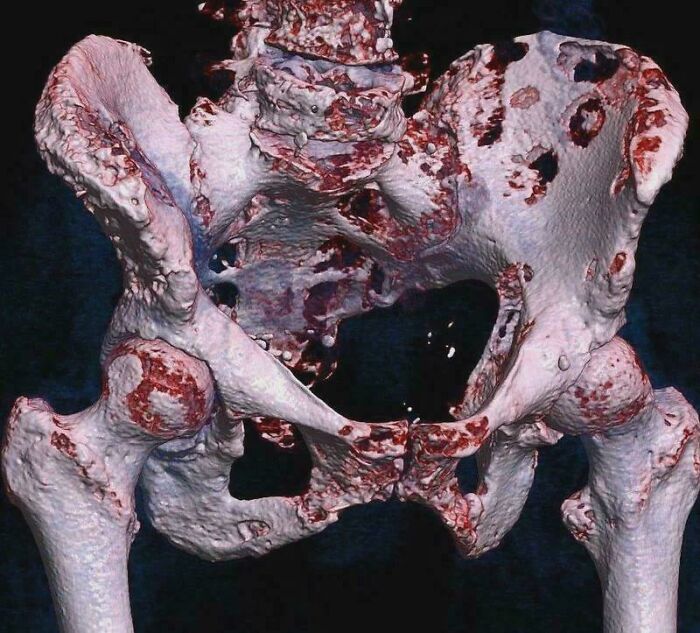

This Photo Shows A 3D Rendered CT Scan Of Bone Metastases Of The Hip Bone, In A 60-Year-Old Woman With Parotid Gland Cancer

Large lesions are seen on the ilium on the more distant side. Involvement of the vertebral column has caused a compression fracture.